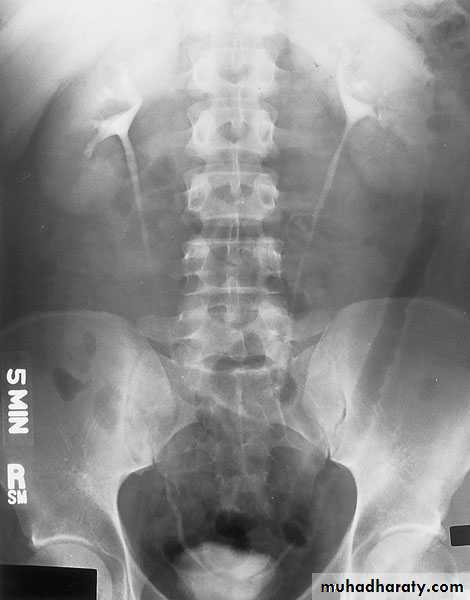

EXCRETORY UROGRAPHY (IVU , IVP, EXU )

These are organic chemicals to which iodine atoms are attached to absorb X-rays.Allows visualization of the entire urinary tract. The study provides demarcation of the renal parenchyma, the pelvicalyceal system, ureters, and bladder, providing both anatomic and functional information.

Number, size, site, function of the kidneys, anatomy of the collecting system, hydronephrosis, and filling defects, stones.

Intravenous urography (IVU)

- After a plain film, iodine-containing contrast medium is injected intravenously and serial films are taken to follow its excretion by the kidneysThe nephrogram phase - on the initial film 1-3 minutes after injection, contrast medium is in the glomeruli and proximal tubules so that a clear image of the renal outline is obtained

The pyelogram phase - subsequent excretion of contrast medium outlines the collecting systems, renal pelvis, ureter and bladder, showing any structural abnormalities or filling defects